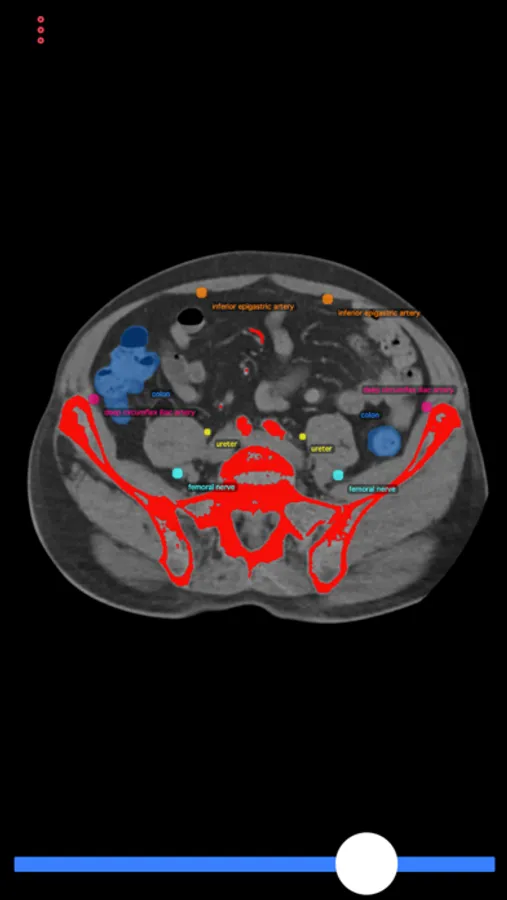

This app consists of body-CT scan (computer-tomography), which demonstrates possible puncture sides and anatomical structures to avoid during the interventions. The user can scroll through the cross sections of the CT scan to find the ideal puncture access.

This app can guide interventional and general radiologists, but also general practitioners or any diagnostic doctor to perform a safe biopsy or drainage catheter placement without injuring the patients.

Biopsy Guide Screenshots

Screenshot 1Screenshot 2Screenshot 3